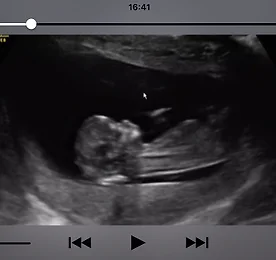

(10/29) 12주 1일 처음 보는 정밀 초음파 시간이 또 훅 가고 만난 건 첫 정밀 초음파!정말 몇 주 안지났는데 인간의 형태를 완벽하게 갖춘 걸 보고 엄청 놀랐던 기억이 난다..(느낌은 전혀 없지만) 나름 꼼지락 하기도 하고, 팔다리도 휘젓고, 눕는 방향도 바꾸고, 입도 오물오물하는..(이런게 모두 초음파로 잡힌다는것도 너무 신기하지 않은가!!) 혹시나 성별을 알 수 있을 수도 있다는 주수인 12주차였지만, 초음파 봐주는 선생님이 매우 꼼꼼하게도 다리 아래는 안보시더라는 ㅋㅋ이때부터 나의 걱정과 조바심은 시작되었는지도 몰라(...).. 더보기